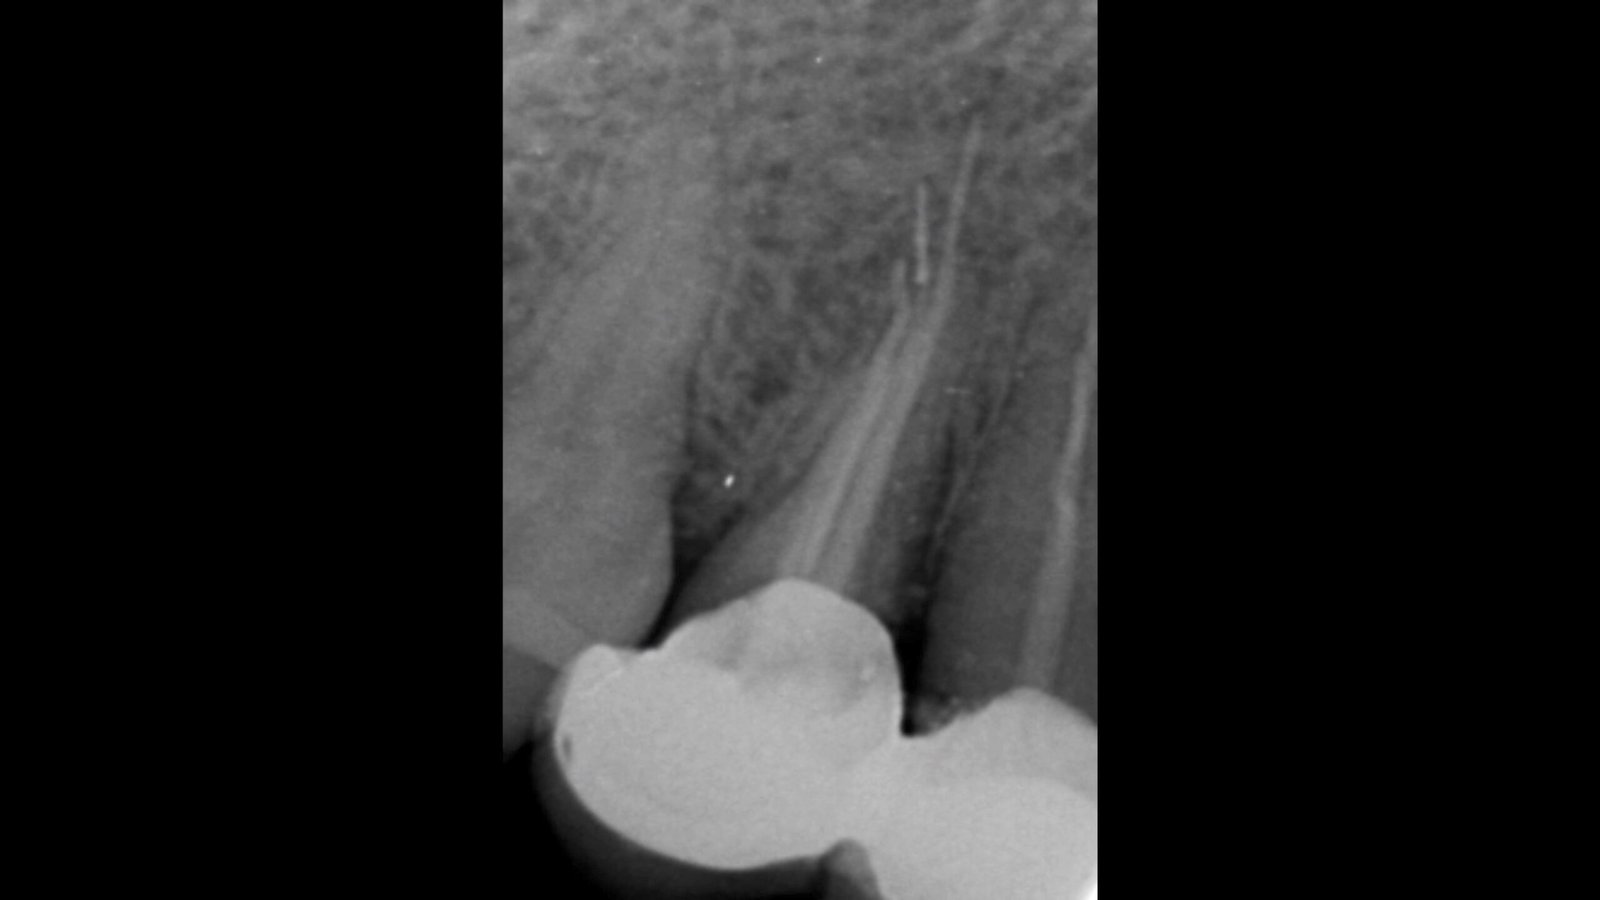

A patient visited our clinic, complaining of pain and occasional swelling on her face after a previous root canal treatment on her right premolar tooth. During our examination and X-rays, I discovered that the earlier dentist had overfilled the canal and, more seriously, had broken a canal shaping file beyond the end of the root, deep into the surrounding bone—showing a lack of proper root canal technique. The X-rays revealed that about 5% of the broken file was still in the canal, while the rest was lodged in the bone.

I then extracted the tooth, which showed overfilled canals, but unfortunately, the broken file did not come out with the tooth. A follow-up X-ray confirmed the file remained in the bone. Using a high-magnification microscope and special illumination, I performed a surgical procedure to carefully remove the broken file from the bone. The patient’s discomfort was resolved after a few days, and she recovered well.